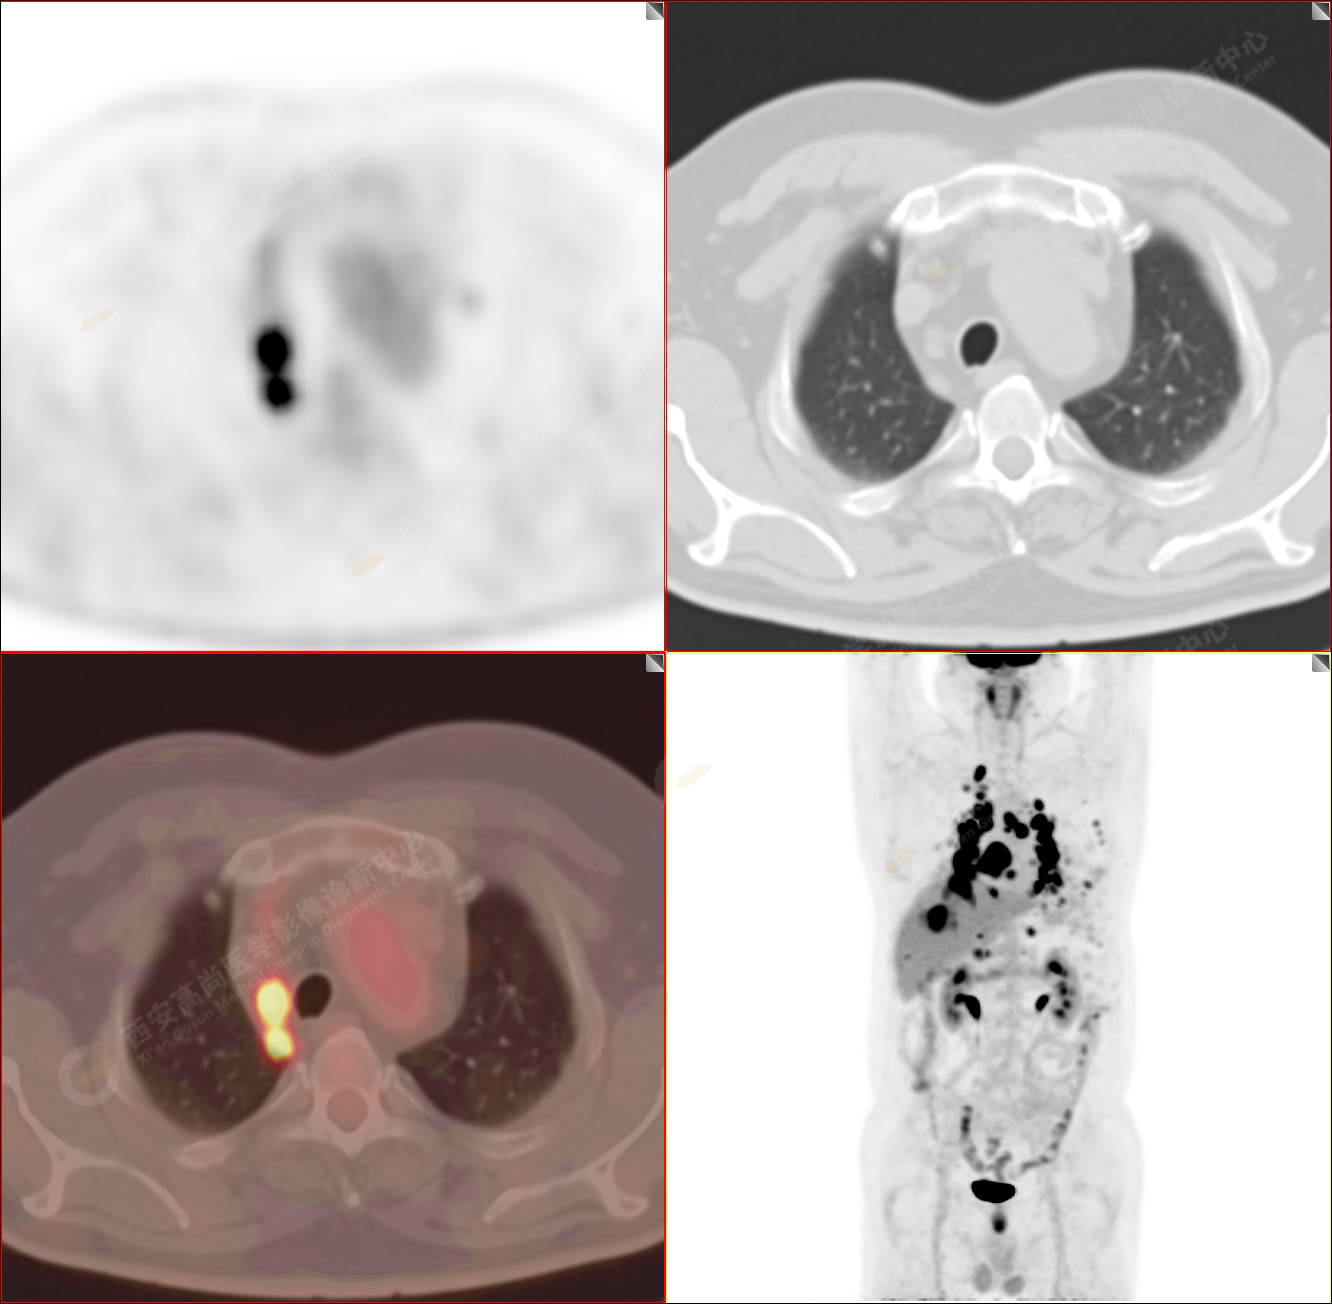

男性,53歲,頭暈半月入院,CT發(fā)現(xiàn)肺內(nèi)腫塊,雙肺多發(fā)大小不等實(shí)性及粟粒樣結(jié)節(jié),雙肺門(mén)及縱隔多發(fā)腫大淋巴結(jié)。病程中無(wú)發(fā)熱、胸悶氣及胸部不適。既往:左側(cè)肋骨外傷史。

PET/CT圖像